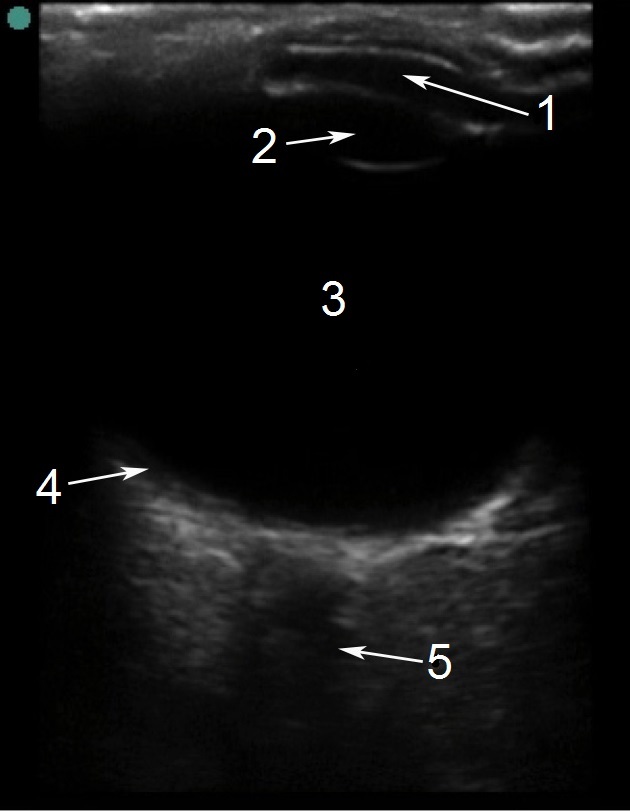

眼部正常解剖结构 1 图像

前房

晶状体

玻璃体

视网膜

视神经